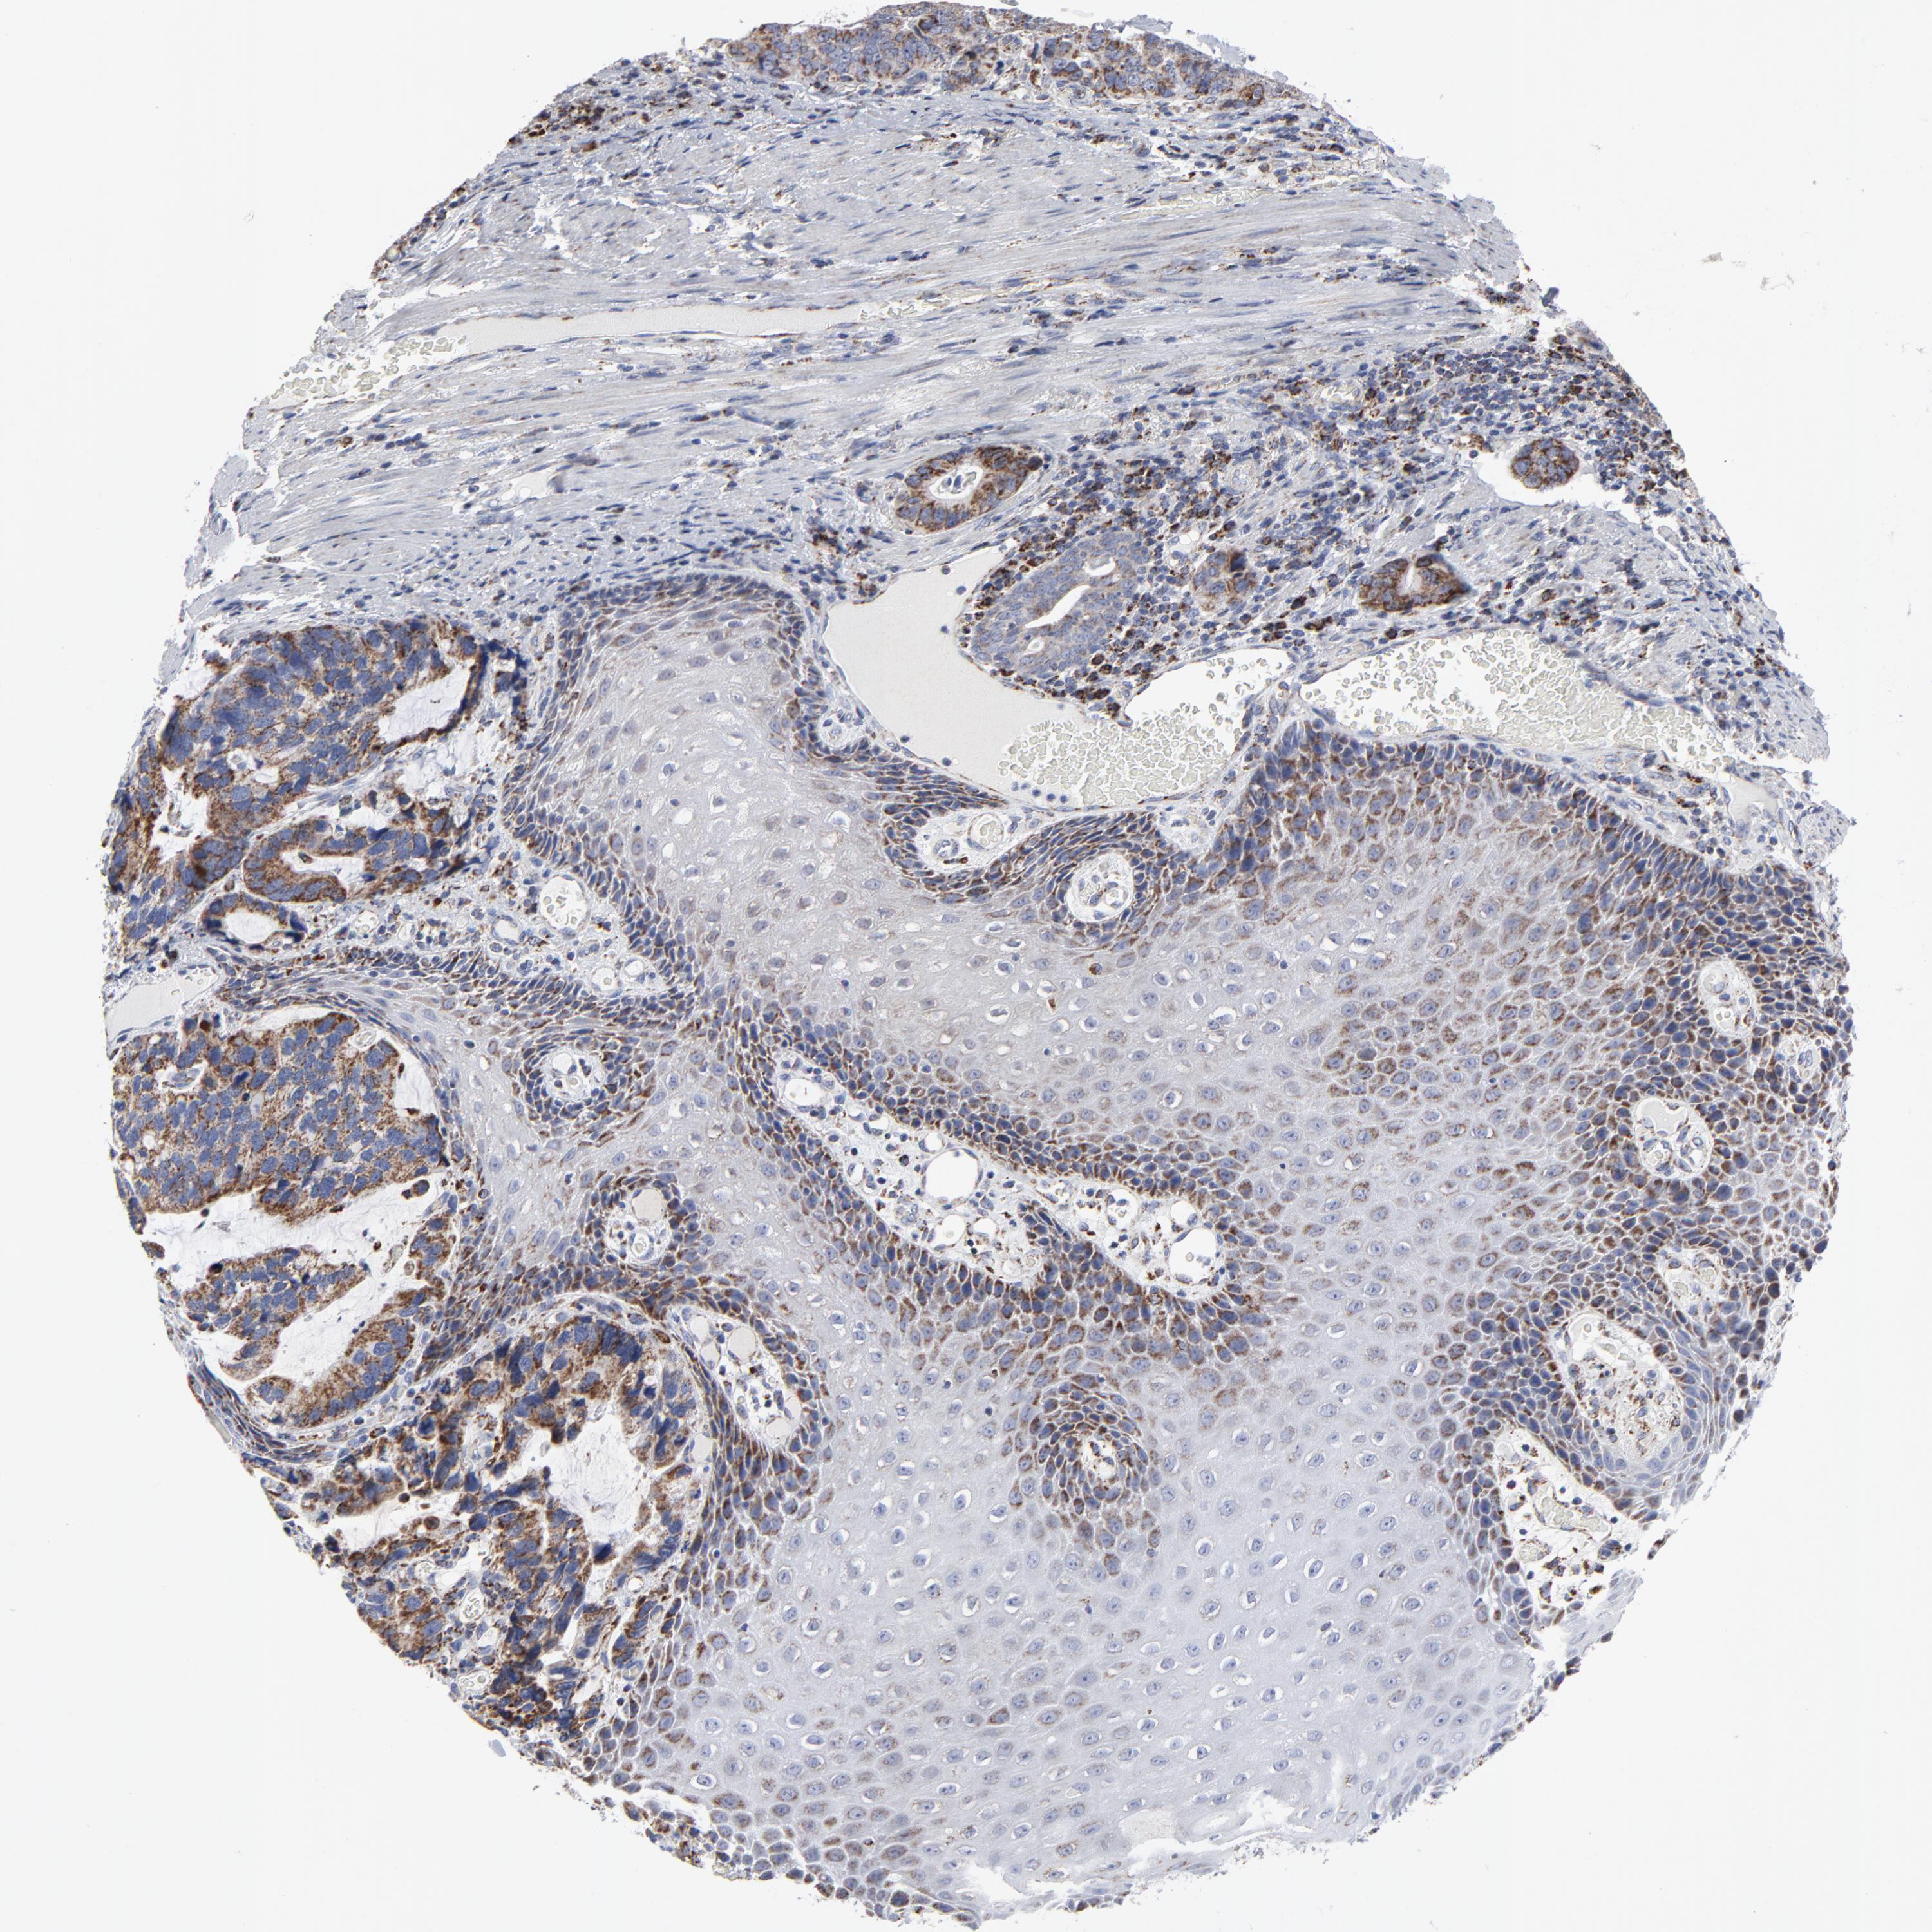

STOMACH CANCER - Protein expressioni

A mouse-over function shows sample information and annotation data. Click on an image to view it in a full screen mode. Samples can be filtered based on level of antibody staining by selecting one or several of the following categories: high, medium, low and not detected. The assay and annotation is described here.

Note that samples used for immunohistochemistry by the Human Protein Atlas do not correspond to samples in the TCGA dataset.

Antibody stainingi

Antibody staining in the annotated cell types in the current human tissue is reported as not detected, low, medium, or high, based on conventional immunohistochemistry profiling in selected tissues. This score is based on the combination of the staining intensity and fraction of stained cells.

Each image is clickable and will lead to virtual microscopy that enables deeper exploration of all samples and also displays staining intensity scores, fraction scores and subcellular localization as well as patient and tissue information for each sample.

Antibody HPA003323

Antibody CAB002007

Staining

High

Medium

Low

Not detected

Intensity

Strong

Moderate

Weak

Negative

Quantity

>75%

75%-25%

<25%

None

Location

Nuclear

Cytoplasmic/membranous

Cytoplasmic/membranous,nuclear

Adenocarcinoma, NOS